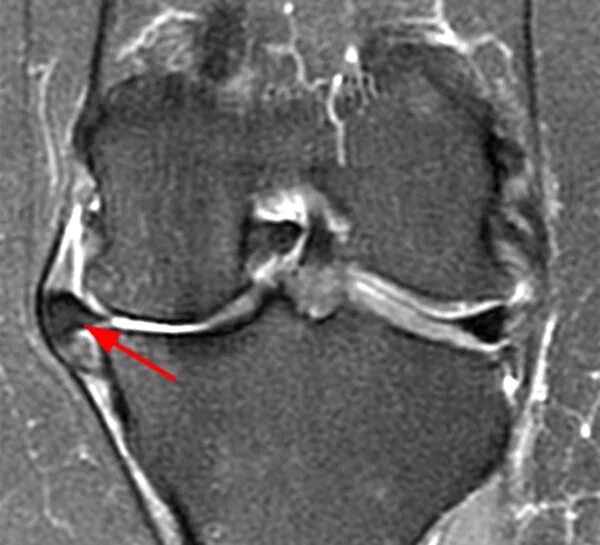

Повреждение мениска мрт